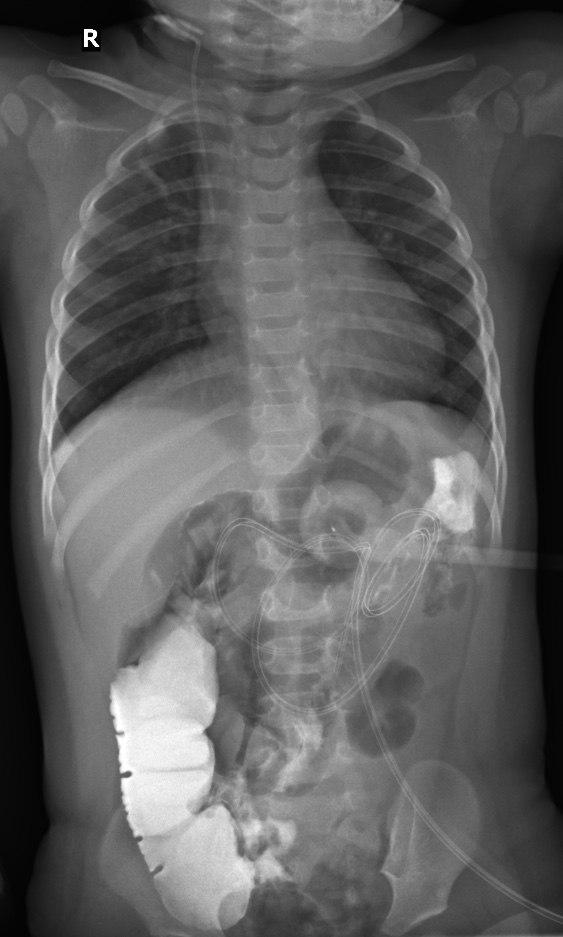

- Рентген, рентгеноскопія: Створює двовимірне зображення кісток. Швидкий та простий метод, але показує не всі деталі.

Рентген, рентгеноскопія: Швидкий та доступний для виявлення переломів, вивихів та інших проблем з кістками.

- Комп’ютерна томографія: Siemens SOMATOM X.cite (128 зрізів, мах. 364 реконструйовані зрізи)